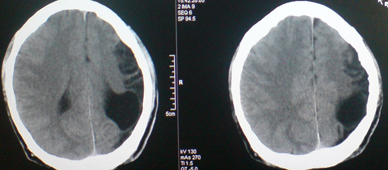

标题: CT24297:患者,男,左手抽搐致摔倒,平时无不适。 [打印本页]

标题: CT24297:患者,男,左手抽搐致摔倒,平时无不适。

1.左侧顶叶脑软化并脑脑穿通畸形,左侧大脑半球萎缩。2.左侧外侧裂蛛网膜囊肿。

以下是引用yulanhua在2010-1-23 16:19:00的发言:[br]1.左侧顶叶脑软化并脑脑穿通畸形,左侧大脑半球萎缩。2.左侧外侧裂蛛网膜囊肿。

1、左侧颞顶叶脑软化灶。2、左侧大脑半球萎缩。没有其他病史吗?

左颞顶叶脑萎缩,左外侧裂蛛网膜囊肿。

颜面血管瘤? 胼胝体发育不全。